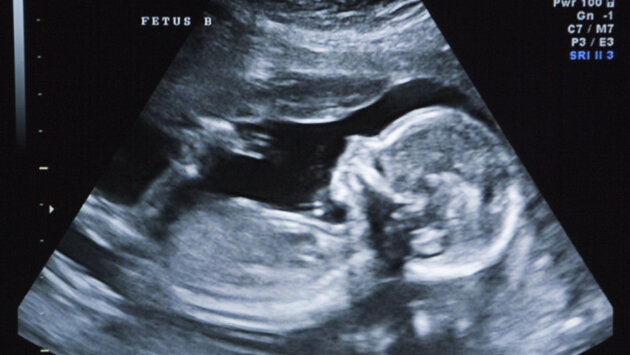

Джессика Аллен, мать двоих детей, согласилась стать суррогатной матерью для бесплодной пары из Китая. Спустя шесть недель после успешной процедуры ЭКО во время проведения УЗИ врачи обнаружили два плода.